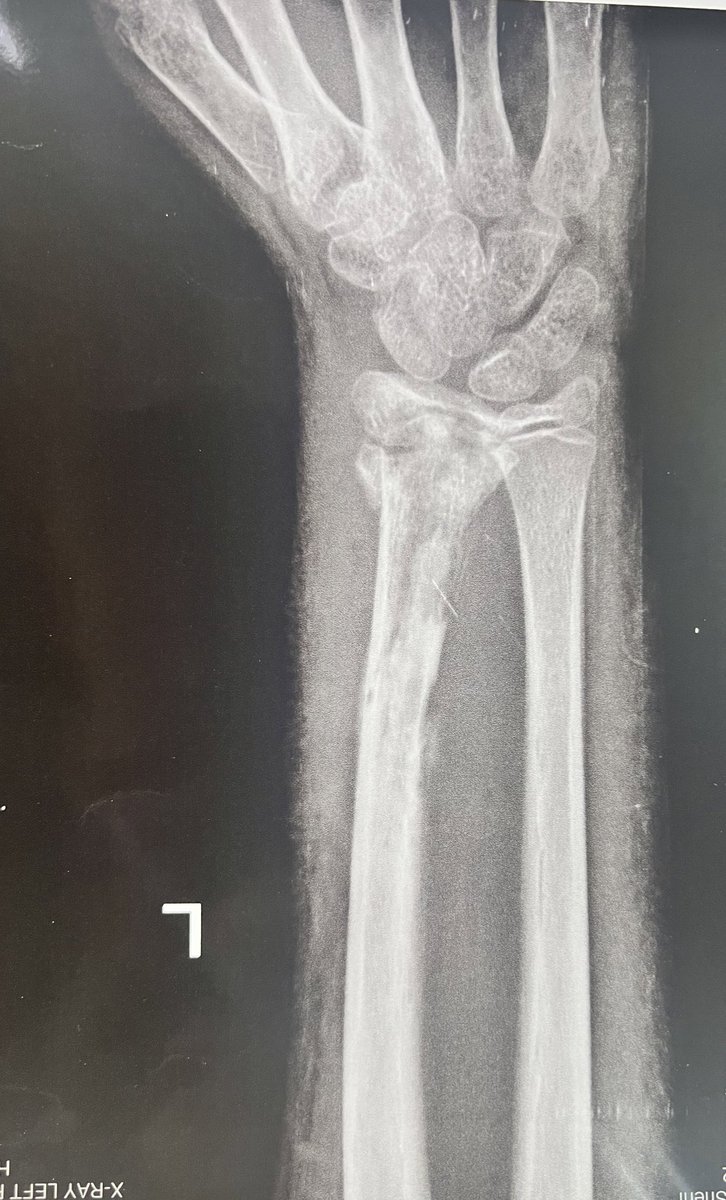

بعد ٣ اسابيع فقط ظهر الم و تورم و دي الاشعة الحديثة (كارثة) التهاب صديدي و خراج و سوسة بالعظام، هيتم الشرح 👇

مع استمرار الاعراض تم اكتشاف التهاب صديدي و تأكل بالعظم و صديد ضرب معظم العظم مع تأكل ٥ سم من الكعبرة 👇